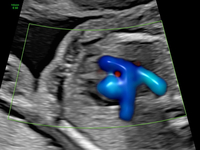

In der Regel wird für diese Untersuchung eine Überweisung vom betreuenden Frauenarzt ausgestellt, z. B. wenn im Rahmen der üblichen in den Mutterschaftsrichtlinien empfohlenen Ultraschalluntersuchung eine Auffälligkeit gesehen wurde. Weitere Gründe für eine Überweisung sind Risikoschwangerschaften oder auch der Wunsch der Eltern nach einer zusätzlichen Absicherung. Neben der allgemeinen Entwicklung des Kindes können hier –noch genauer als im Ersttrimesterscreening – alle Organe des ungeborenen Kindes begutachtet werden. Zusätzlich wird mittels Dopplersonographie die kindliche Versorgung und die des Mutterkuchens überprüft. Da Herzfehlbildungen zu den häufigsten angeborenen Fehlbildungen gehören, stellt die detaillierte fetale Echokardiographie (Untersuchung des kindlichen Herzens) einen wichtigen Bestandteil der Untersuchung dar. Dabei werden sowohl die Anatomie des Herzens als auch die Blutflüsse begutachtet.

Echokardiografie